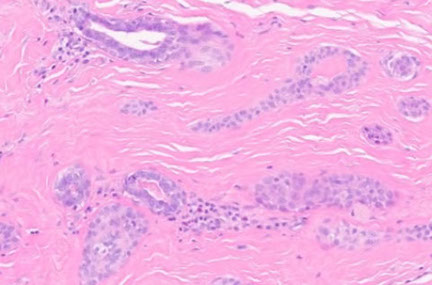

Cylindroma

- aka turban tumor

Kinda common b9 adnexal tumor of head/neck that appears as papules or nodules as a slow-growing and usually solitary tumor that is generally painless; etiology is unknown; F>>M

- may be assoc c AD Brooke-Spiegler syndrome if multiple in the dz's facial trichoepithelioma and eccrine poroma

Gross: looks like brain gyri

Gene: CYLD gene mutations cr 16q12-13

Micro: islands of basaloid cells in jigsaw pattern c scant cytoplasm surrounded by thick pink hyaline membrane and hyaline droplets bwt islands

- 2 types of epithelial cells peripheral cell (large basophilic nucleus which palisades); pilar cell (centrally located c vesicular chromatin pattern)

Tx: simple surgical excision can be curative

Px: excellent

- rarely can transform to a malignant lesion